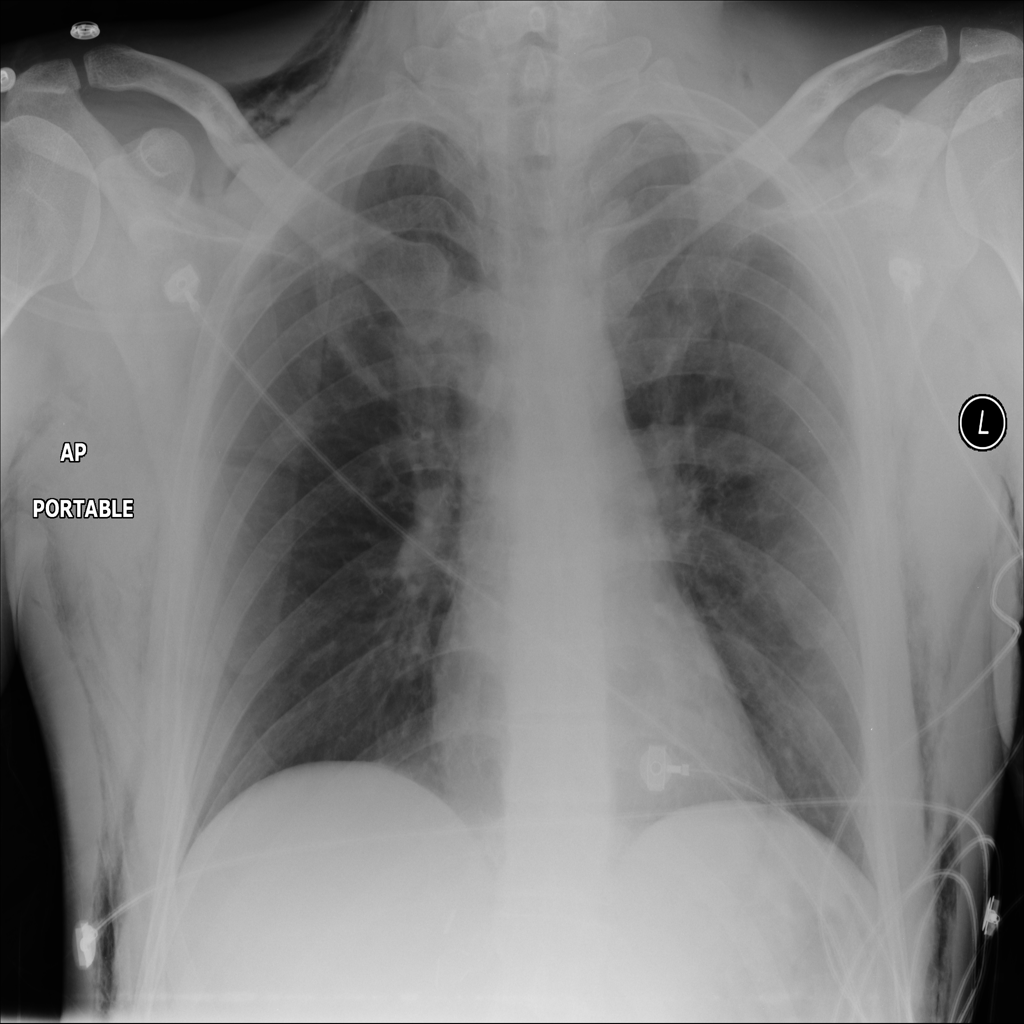

PAT-0E82 · IMG-000Emphysema

PAT-0E82 · IMG-000

AP